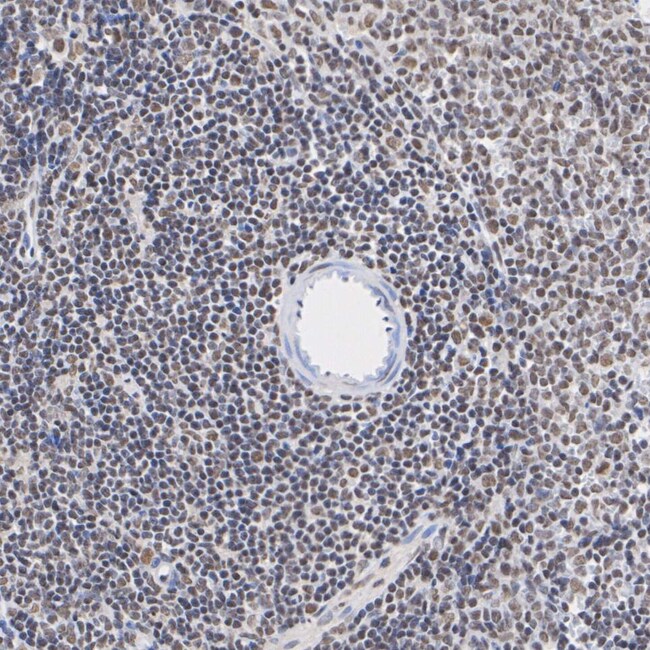

Phospho-AKT1/AKT2/AKT3 (Ser473) Recombinant Monoclonal Antibody for Western Blot, IHC (P), Flow

Applications Flow Cytometry, Immunohistochemistry (Paraffin), Western Blot

Immunogen Synthetic phosphopeptide corresponding to residues surrounding Ser473 of human Akt1.